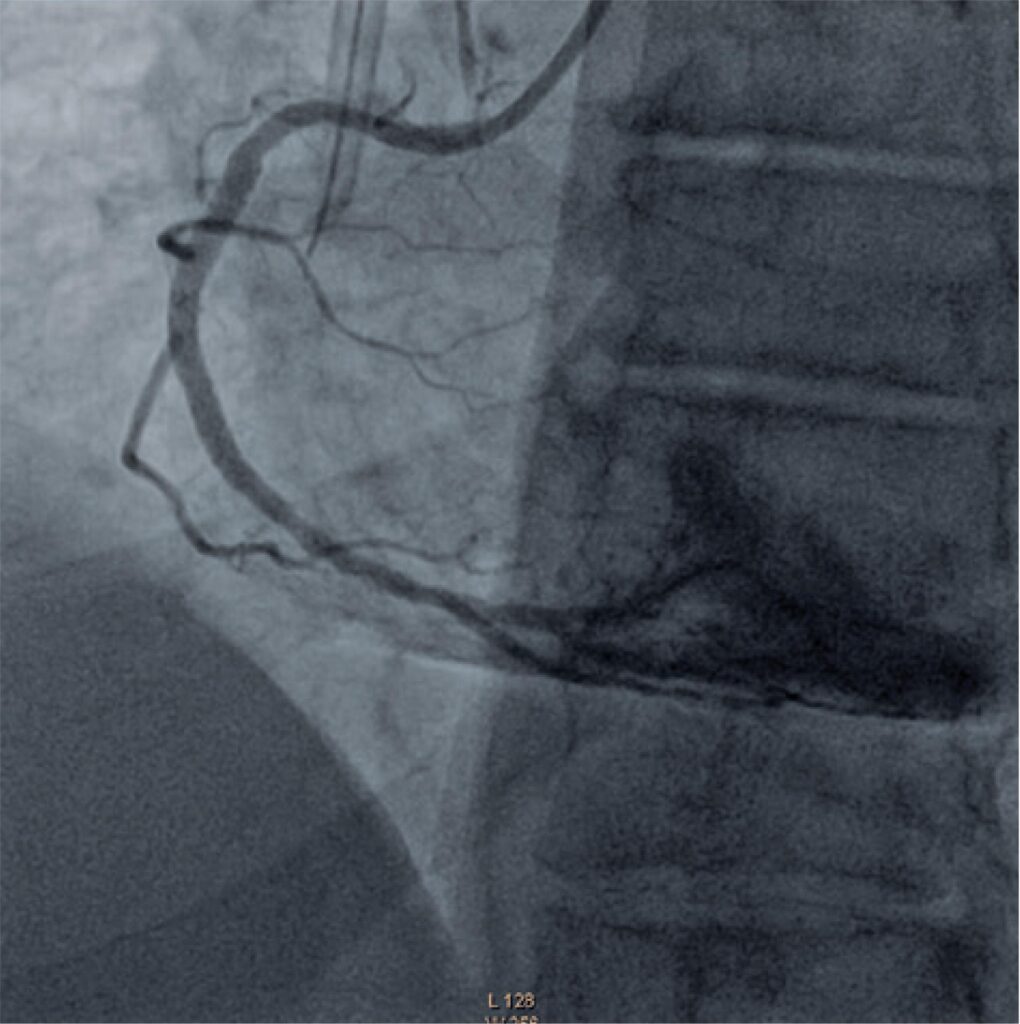

Paciente hemofílico com doença arterial coronariana em pré-operatório de transplante de fígado

As hemofilias A e B, apesar de raras, são os distúrbios de coagulação que mais ocorrem em homens. Com o advento das profilaxias e a melhoria da terapia de reposição do fator de coagulação, pacientes com hemofilia têm atingido expectativa de vida semelhante à da população geral, levando ao aumento dos fatores de risco cardiovasculares e à consequente doença aterosclerótica coronariana. A necessidade de terapia antiplaquetária e anticoagulante nesses pacientes aumenta ainda mais a tendência a sangramentos. Evidências e recomendações para esses pacientes em procedimentos como intervenção coronária percutânea são escassos na literatura.